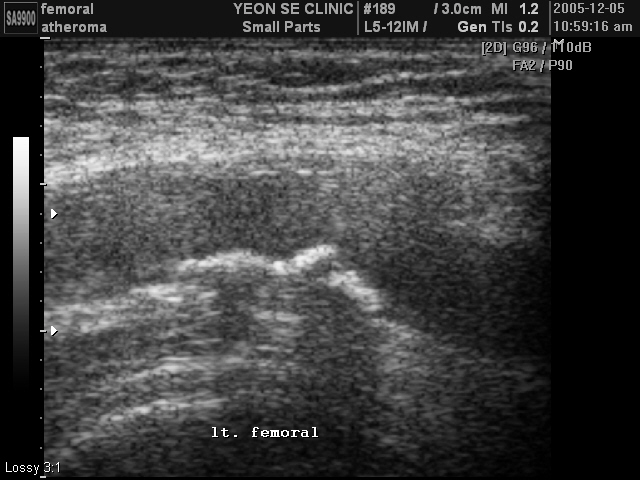

Ultrasonographic data of our patients

Femoral at...